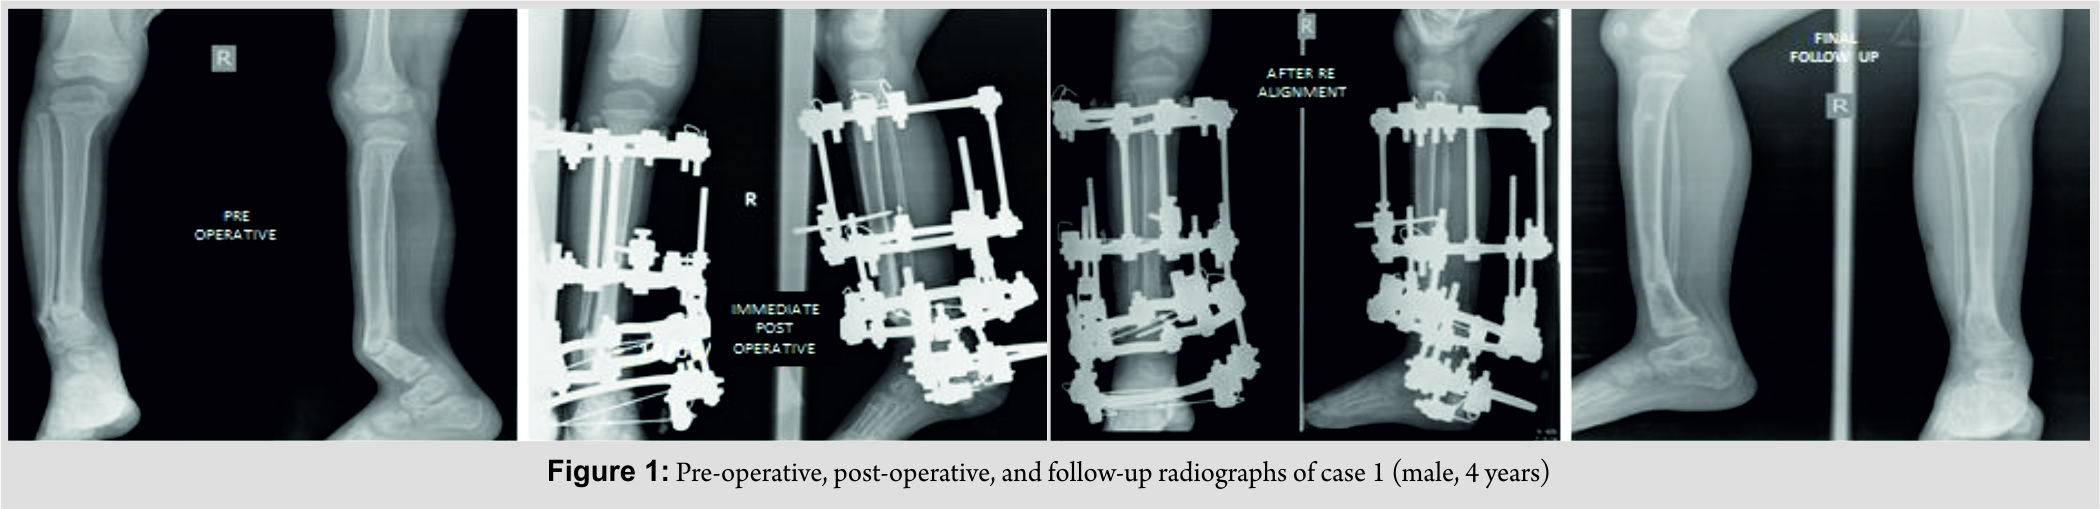

We had four children (3 males and 1 female, age 4–15 years) with hypertrophic nonunion of the tibia. Three of them were post-traumatic. The fourth patient had tibial bone defect following acute osteomyelitis. He underwent tibialisation of the fibula elsewhere. The distal junction united uneventfully, but the proximal junction went in for hypertrophic nonunion. The demographic and clinical characteristics of our patient cohort are summarized in Table 1 (Fig. 1, 2, 3, 4).

All patients had a follow-up of 2 years from the removal of external fixator. All four non-unions united uneventfully. In the two patients were deformity correction was completed in two stages, compression commenced after 3 days after second surgery. (No manipulation was done during the week in between two stages as it would inadvertently stretch the soft tissue.) Another patient (where all deformities were acutely corrected) developed minimal swelling of the limb and blebs on the 2nd day. It responded to limb elevation and delay of rehabilitation. Compression was started after a latent period of 7 days. In the fourth patient, the latent phase lasted only for 3 days. After completion of “dynamic” phase, patients were sent home with advice to follow-up every 6 weeks. Three of the nonunions were united at the second follow-up (12 weeks) and the fourth at third follow-up (18 weeks). Thus, the total duration of external fixator was 14 weeks in one patient, 15 weeks in two patients, and 21 weeks in the fourth patient. The fixators were removed after satisfactory stress test after loosening all connecting rods. Patellar tendon bearing cast was given for all cases for 6 weeks with the advice of full weight-bearing. Apart from limb swelling and blebs in one case, another patient had pin tract infection that was detected at first follow-up that needed a week of dressings and oral antibiotics. The infection settled uneventfully without any need of wire exchange. Two patients each had minimal residual deformity and shortening <1 cm, well within acceptable limits with potential to remodel. The intraoperative, post-operative, and follow-up characteristics of our patient cohort are summarized in Table 2 (Fig. 1, 2, 3, 4).

The fixators were removed after satisfactory stress test after loosening all connecting rods. Patellar tendon bearing cast was given for all cases for 6 weeks with the advice of full weight-bearing. Apart from limb swelling and blebs in one case, another patient had pin tract infection that was detected at first follow-up that needed a week of dressings and oral antibiotics. The infection settled uneventfully without any need of wire exchange. Two patients each had minimal residual deformity and shortening <1 cm, well within acceptable limits with potential to remodel. The intraoperative, post-operative, and follow-up characteristics of our patient cohort are summarized in Table 2 (Fig. 1, 2, 3, 4).